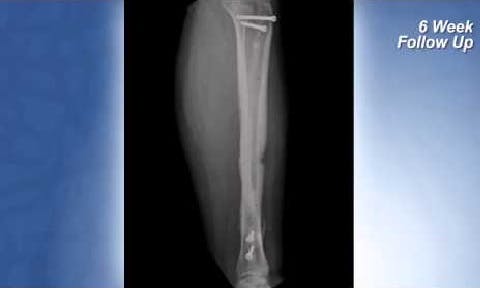

Complex Tibia Fracture

See Dr. Joshua Niemann, M.D. explain the treatment and recovery of a motor vehicle accident trauma patient who received a tibial fracture plate composed of PEEK-OPTIMA Ultra-Reinforced

Experiences of Gil R. Ortega, MD, MPH and Cody Pehrson, MD in Journal of Orthopedic Trauma (JoT) s. This article reviews the unique use of these implants in a collegiate athlete with bilateral, symptomatic tibial shaft stress fractures that failed conservative management, and a patient who suffered an initial, open tibial shaft, and pilon fracture who was surgically treated initially, which then became a nonunion.